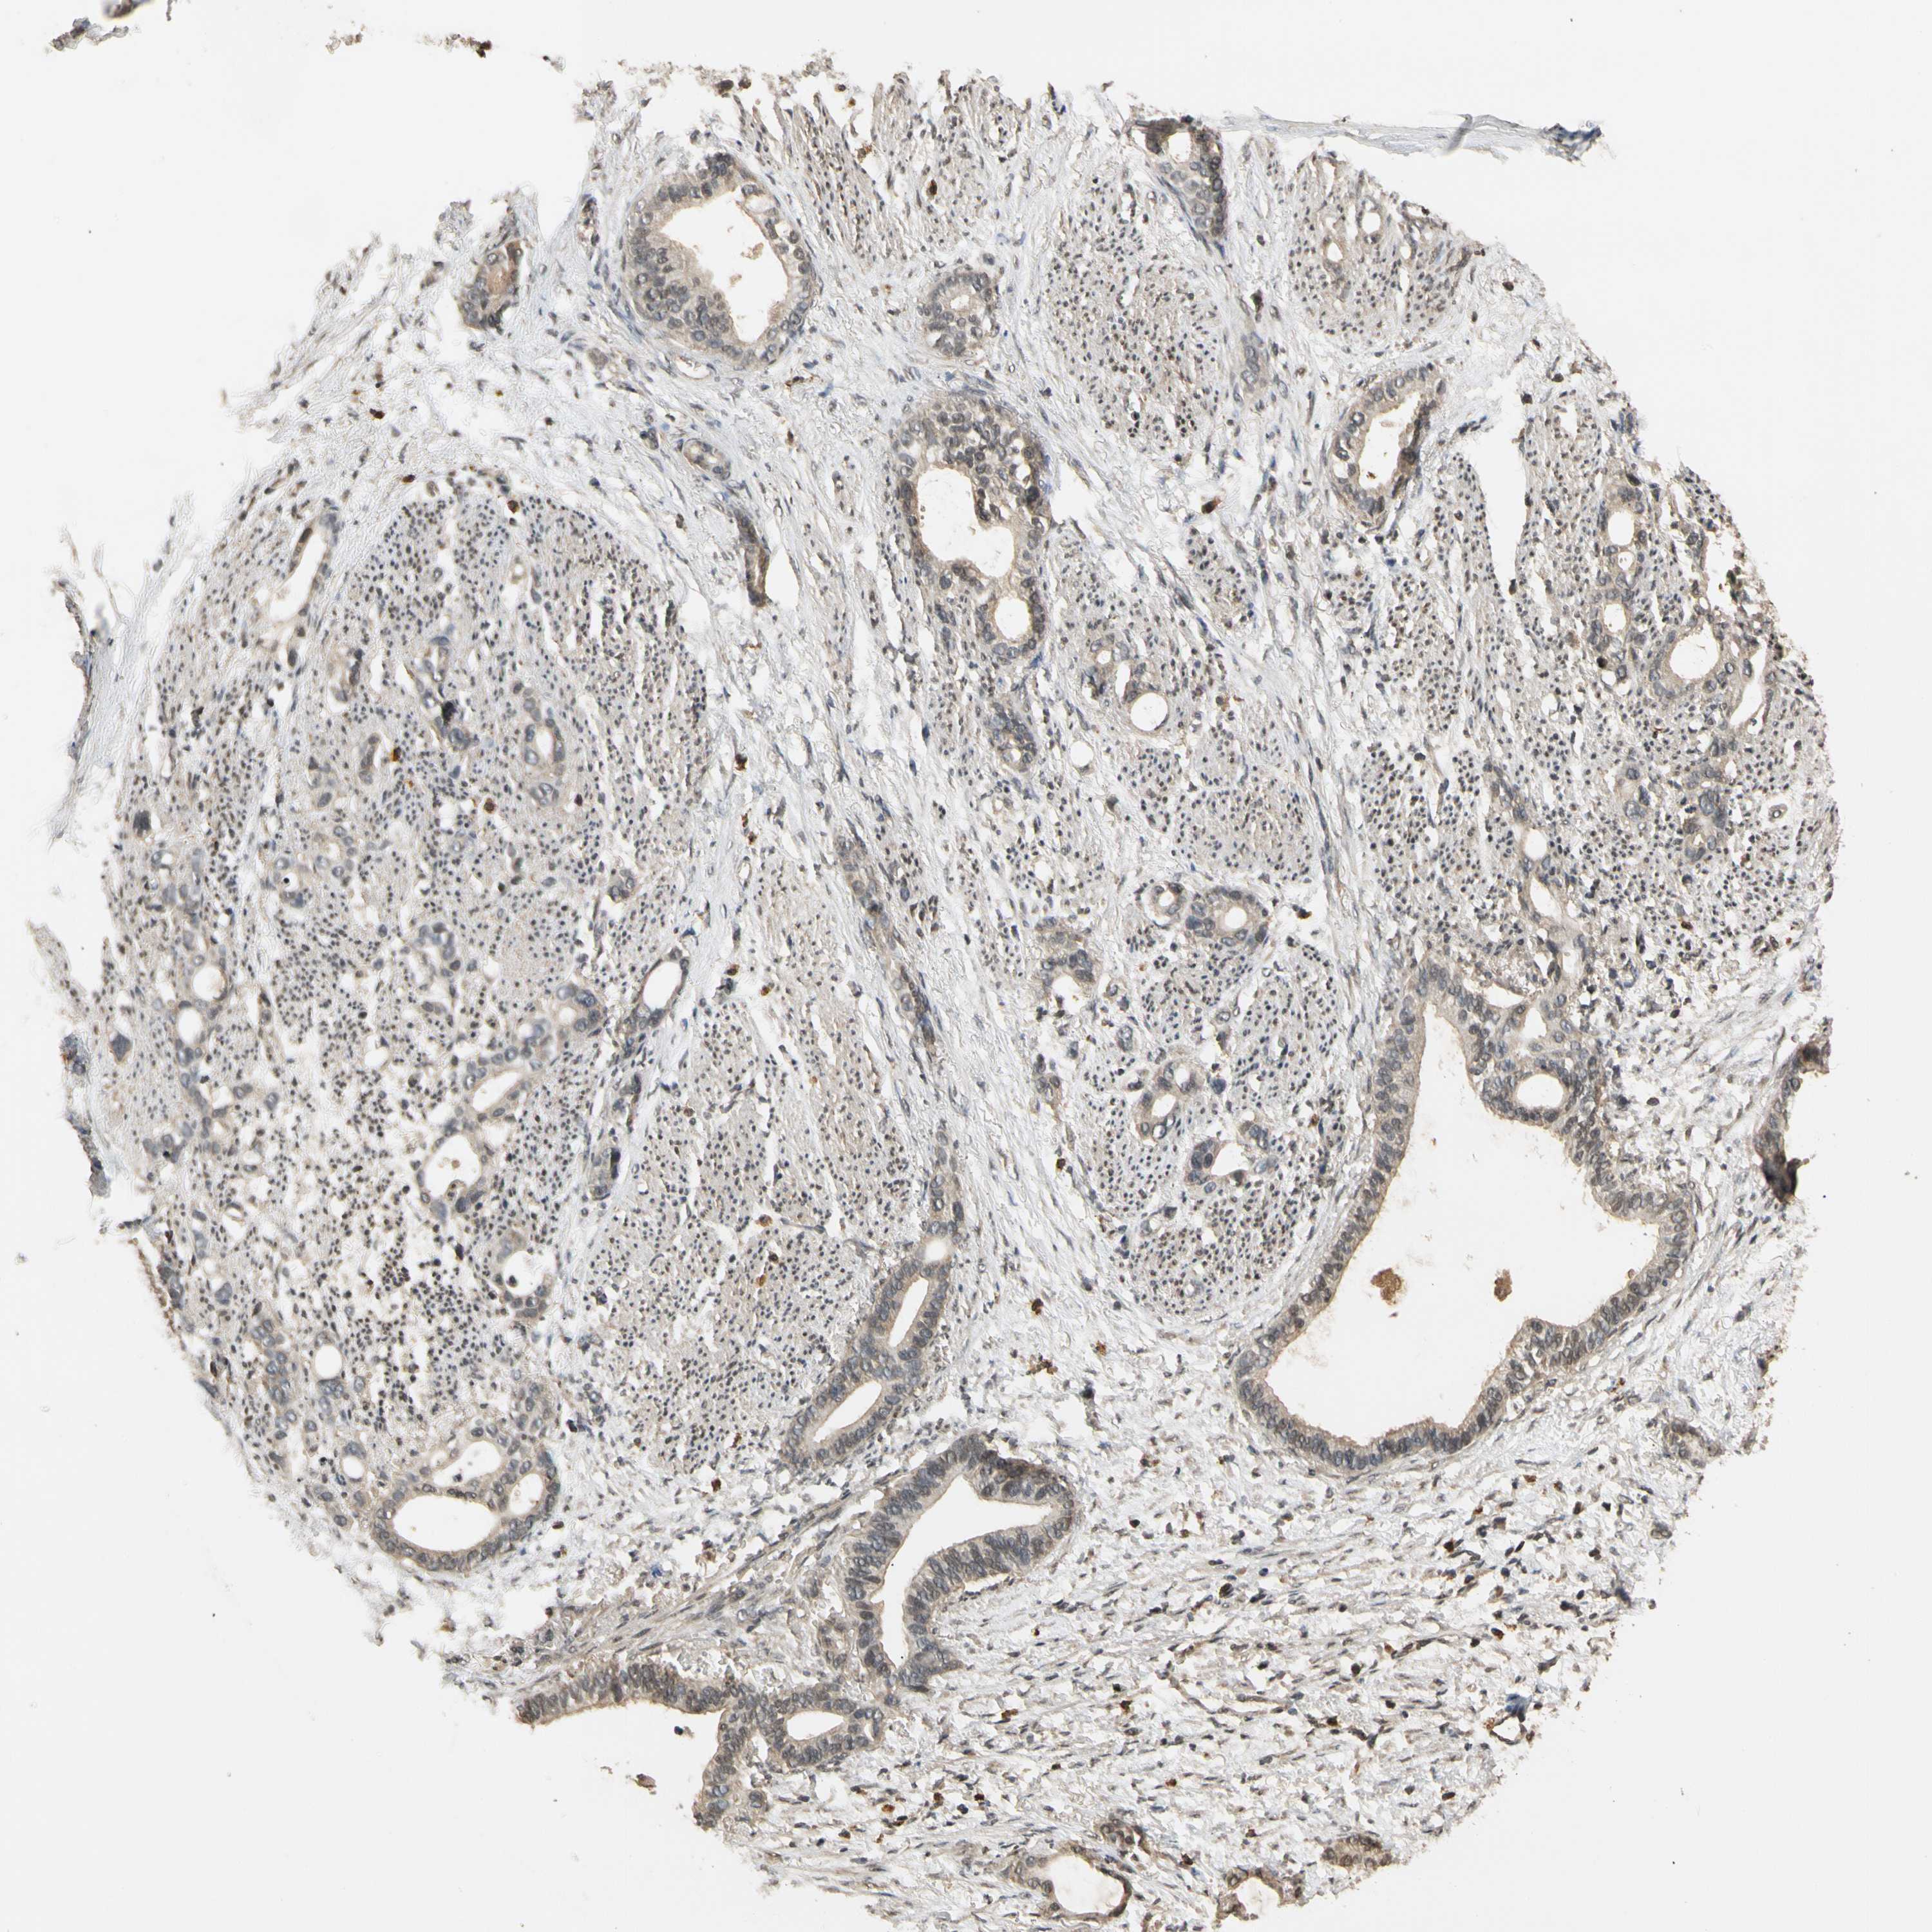

STOMACH CANCER - Protein expressioni

A mouse-over function shows sample information and annotation data. Click on an image to view it in a full screen mode. Samples can be filtered based on level of antibody staining by selecting one or several of the following categories: high, medium, low and not detected. The assay and annotation is described here.

Note that samples used for immunohistochemistry by the Human Protein Atlas do not correspond to samples in the TCGA dataset.

Antibody stainingi

Antibody staining in the annotated cell types in the current human tissue is reported as not detected, low, medium, or high, based on conventional immunohistochemistry profiling in selected tissues. This score is based on the combination of the staining intensity and fraction of stained cells.

Each image is clickable and will lead to virtual microscopy that enables deeper exploration of all samples and also displays staining intensity scores, fraction scores and subcellular localization as well as patient and tissue information for each sample.

Antibody HPA001401

Antibody CAB008670

Staining

High

Medium

Low

Not detected

Intensity

Strong

Moderate

Weak

Negative

Quantity

>75%

75%-25%

<25%

None

Location

Nuclear

Cytoplasmic/membranous

Cytoplasmic/membranous,nuclear

Adenocarcinoma, NOS